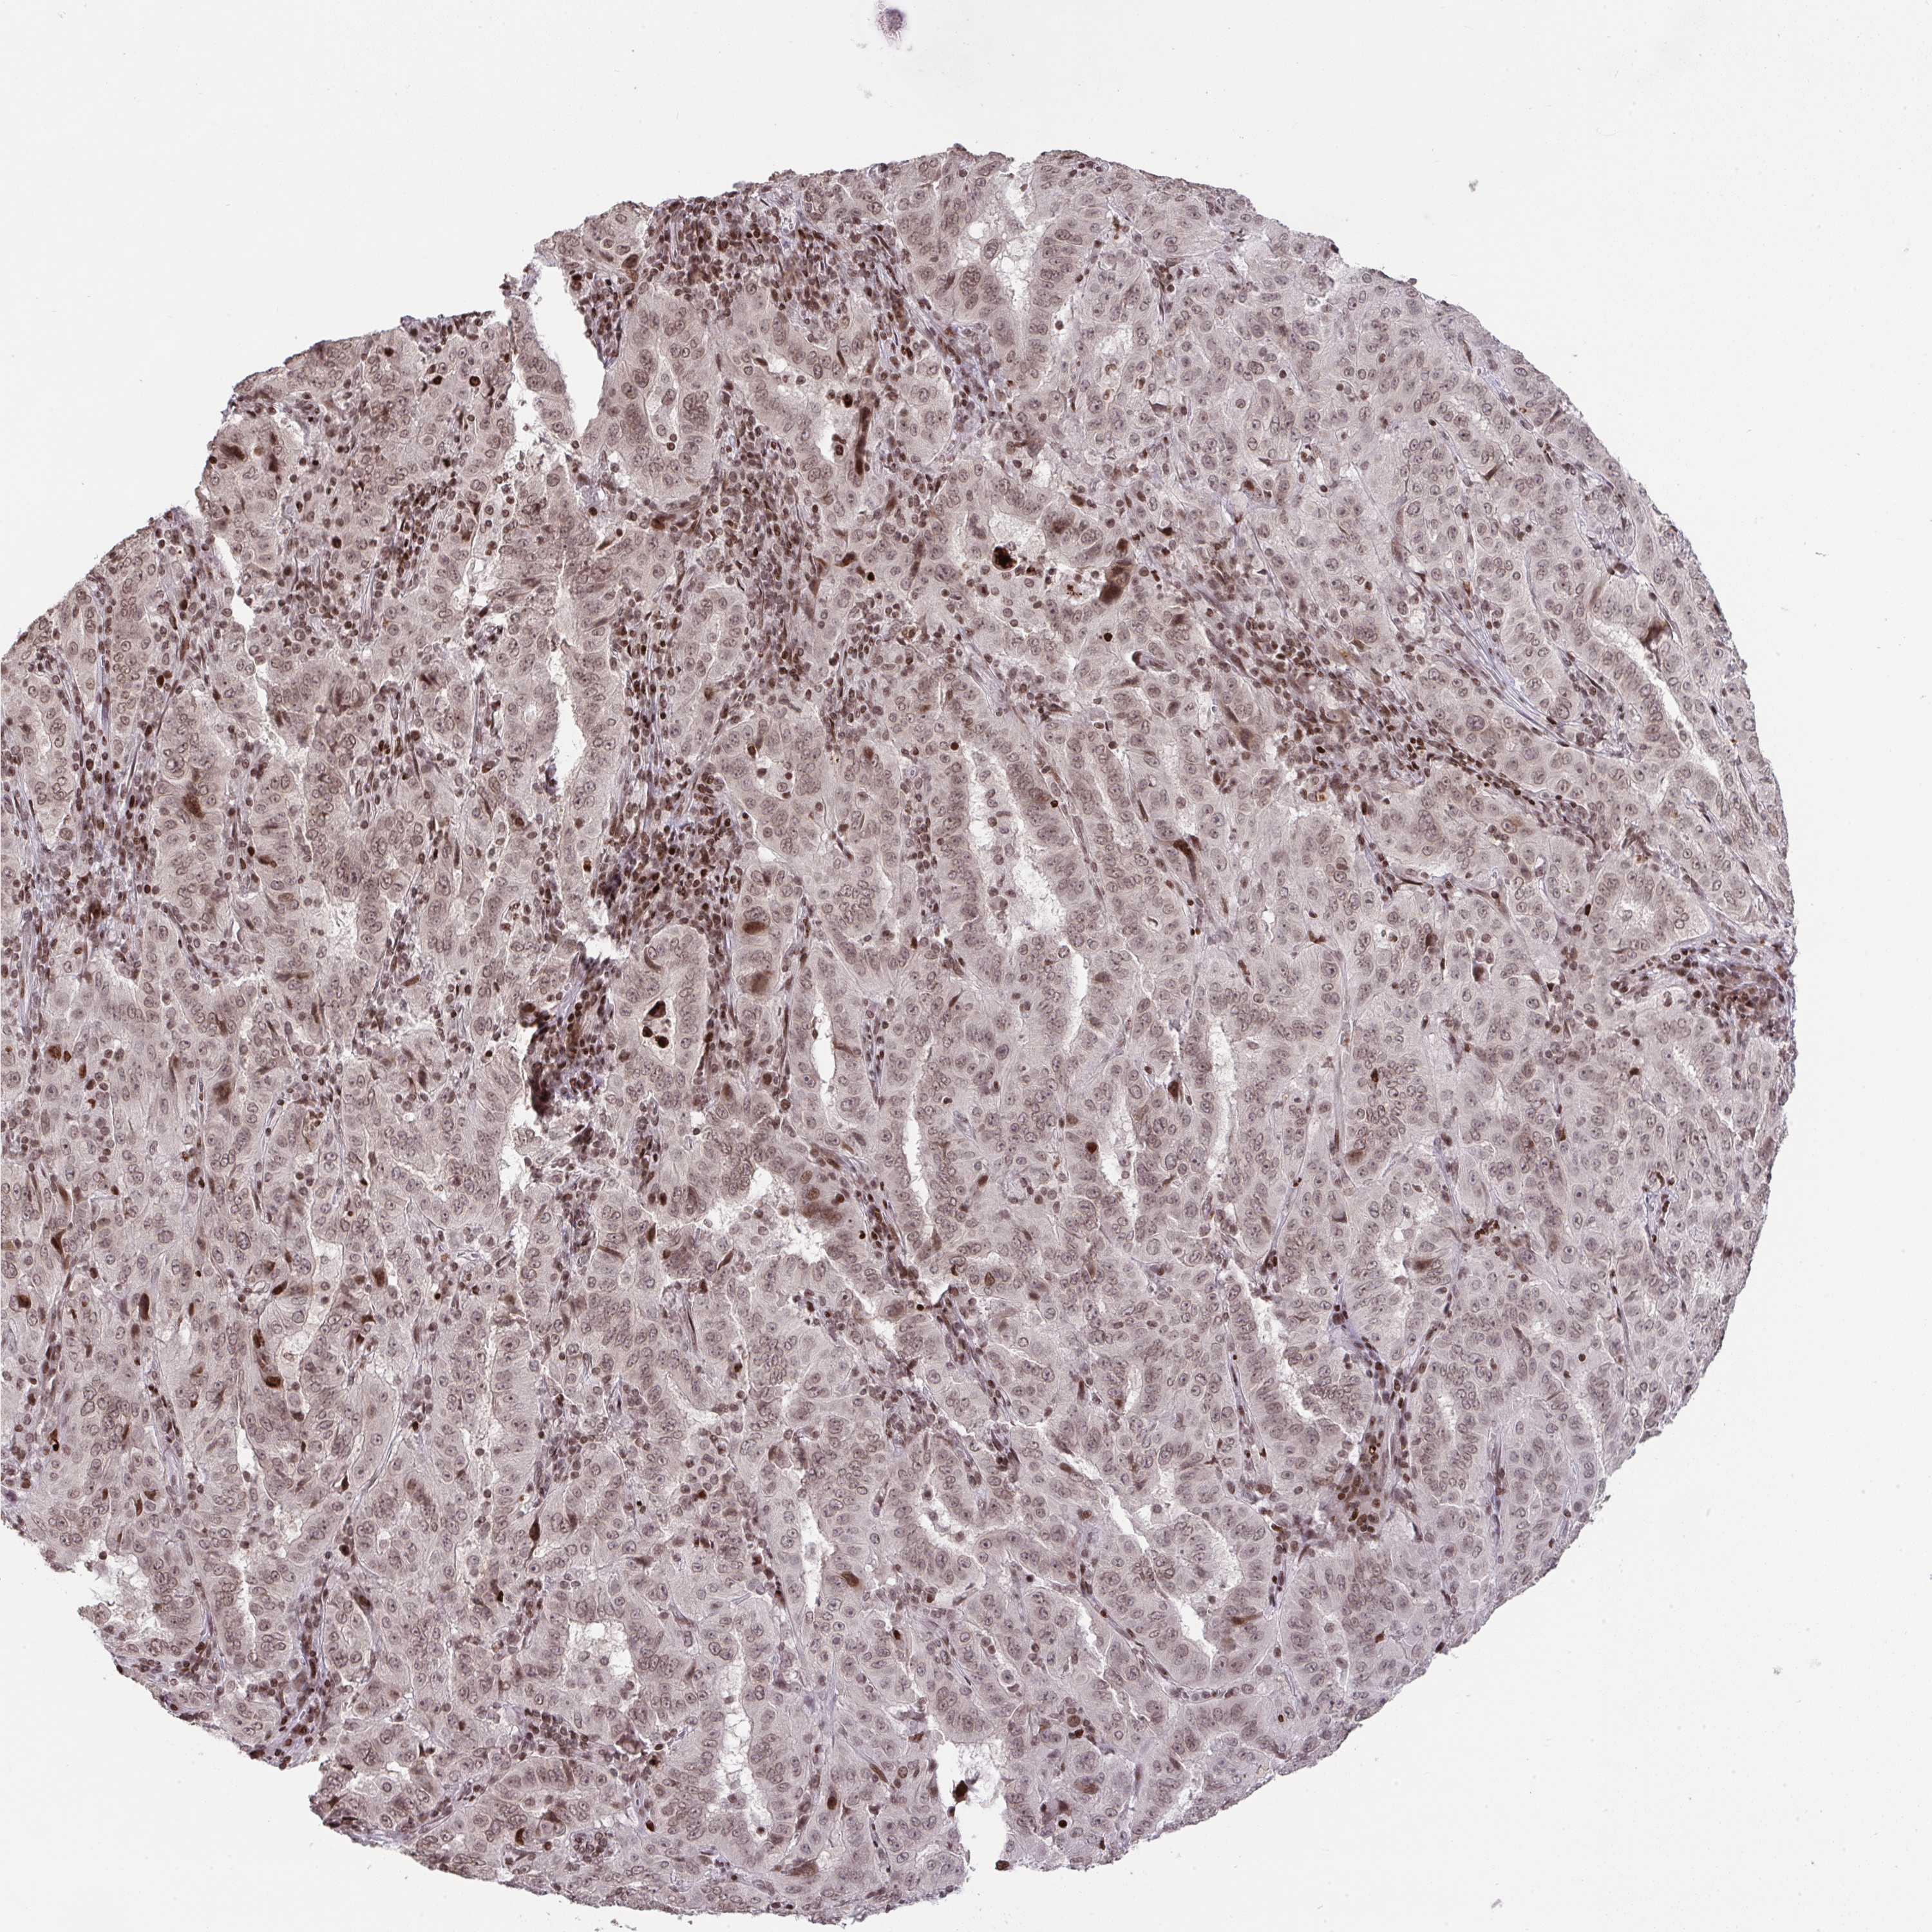

PANCREATIC CANCER - Protein expressioni

A mouse-over function shows sample information and annotation data. Click on an image to view it in a full screen mode. Samples can be filtered based on level of antibody staining by selecting one or several of the following categories: high, medium, low and not detected. The assay and annotation is described here.

Note that samples used for immunohistochemistry by the Human Protein Atlas do not correspond to samples in the TCGA dataset.

Antibody stainingi

Antibody staining in the annotated cell types in the current human tissue is reported as not detected, low, medium, or high, based on conventional immunohistochemistry profiling in selected tissues. This score is based on the combination of the staining intensity and fraction of stained cells.

Each image is clickable and will lead to virtual microscopy that enables deeper exploration of all samples and also displays staining intensity scores, fraction scores and subcellular localization as well as patient and tissue information for each sample.

Antibody HPA059850

Staining

High

Medium

Low

Not detected

Intensity

Strong

Moderate

Weak

Negative

Quantity

>75%

75%-25%

<25%

None

Location

Nuclear

Cytoplasmic/membranous

Cytoplasmic/membranous,nuclear

Adenocarcinoma, NOS